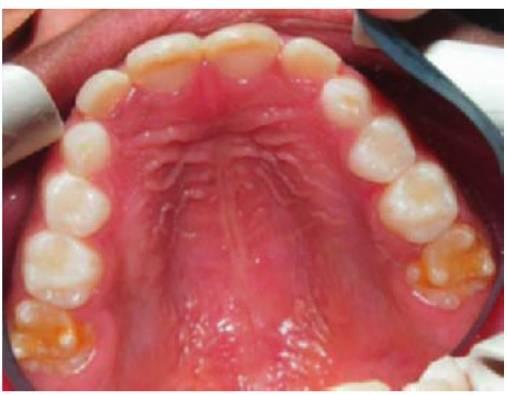

Hipodoncia, oligodoncia y anodoncia son los términos que designan los diferentes grados de progresión de la ausencia de dientes, si bien el término hipodoncia es el más utilizado debido a que se refiere a un número indeterminado de dientes ausentes (fig. 9.1 A). La oligodoncia designa la ausencia de seis dientes o más, y la anodoncia la ausencia completa de dientes. Todos estos casos se producen debido a un fallo en el desarrollo. El término «dientes ausentes congénitamente» no puede aplicarse a la dentición permanente, ya que estos dientes comienzan su desarrollo después del nacimiento, y tampoco a la dentición temporal ya que esa ausencia dental no puede determinarse de forma clínica en el momento de nacer; asimismo, el término «anodoncia parcial» carece de sentido. Sucede con frecuencia que los grados de hipodoncia aparezcan de manera esporádica o bien tengan un componente hereditario. Cuando a un individuo le faltan muchos dientes se debe estudiar a otros miembros de la familia afectados.

Los dientes que faltan con mayor frecuencia son los últimos de cada serie, es decir, el incisivo lateral, el segundo premolar y el tercer molar, y es realmente infrecuente la falta de los incisivos centrales, los caninos o los primeros molares permanentes. En el plano clínico, tiene mayor importancia el tipo de dientes ausentes que su número. La presencia de un diente rudimentario o cónico puede estar asociada a la ausencia del mismo diente del lado opuesto de la arcada. Un ejemplo frecuente es la microdoncia del incisivo lateral, que también puede estar ausente en descendientes del paciente afectado. Las ausencias de dientes son una manifestación de muchos síndromes de cabeza y cuello.

- Varios dientes ausentes (fig. 9.1 B).

Los dientes son pequeños y cónicos y a menudo presentan un gran diastema anterior (fig. 9.3). Sus manifestaciones pueden limitarse a un solo diente ausente o a un incisivo lateral en clavija (v. hipótesis de Lyon, más adelante) y las mujeres heterocigóticas suelen ser diagnosticadas gracias a este tipo de dentición.

Dentro del grupo de displasias ectodérmicas, se observan asimismo modos de herencia autosómica tanto dominante como recesiva. Si se compara con la displasia ectodérmica hipohidrótica ligada al cromosoma X, en las familias con este trastorno no existen diferencias tan acentuadas en cuanto al grado de trastorno entre los hombres y las mujeres (figs. 9.2A, 9.4). Se han identificado mutaciones en el gen MSX1 (4p16.1) en familias con terceros molares y segundos premolares ausentes con o sin paladar hendido/labio leporino, así como en familias con el síndrome diente-uña (Witkop). Se han observado mutaciones del gen PAX9 (14q12-q13) en otras familias con dientes ausentes de forma autosómica dominante.